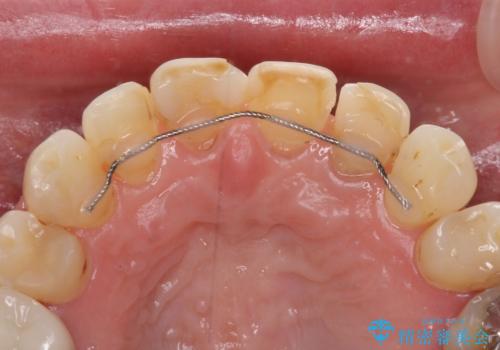

- 前歯の虫歯や治療跡が気になるとのことで来院された患者様です。

以前矯正治療をされ、その時には歯列が整ったので満足されたそうですが、若干の後戻りにより隙間ができ、矯正治療前に治療していた虫歯の跡が気になったため、オールセラミックによる審美治療を希望されました。

目立つ範囲である前歯4歯をオールセラミッククラウンにて補綴することとしました。